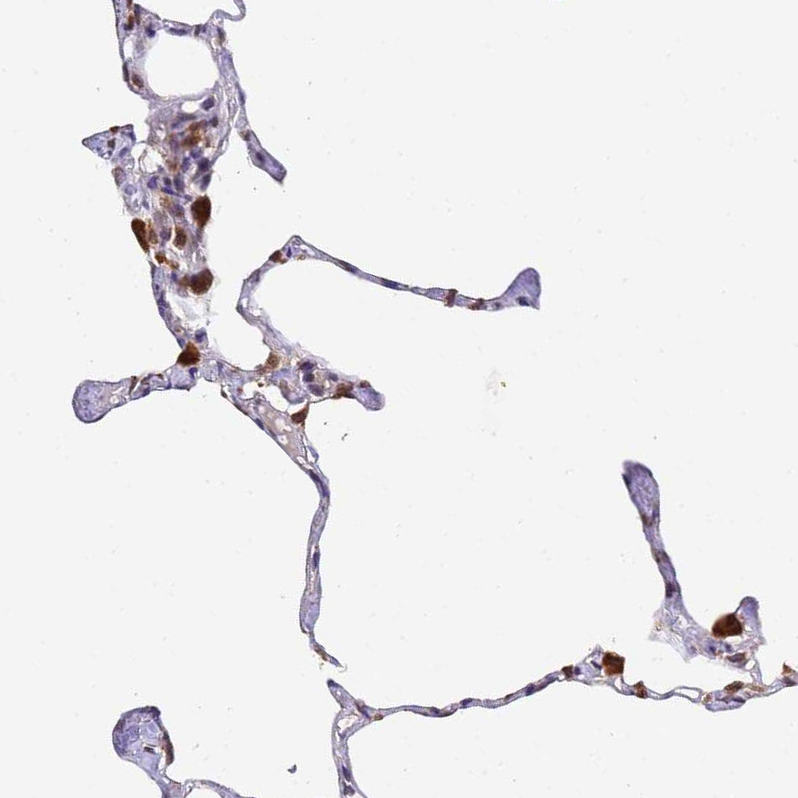

Immunohistochemical staining of human lung shows strong cytoplasmic positivity in macrophages.